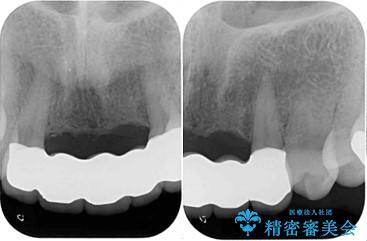

- アンバランスな色や形、歯肉ラインの黒い縁が目立ってしまったブリッジの作り直しを希望して来院された患者様です。

自然な仕上がりとするため、金属を使用しないオールセラミックブリッジにより補綴治療を行うこととしました。

装着されていたブリッジは、支台となっている歯と欠損している歯で色が大きく異なっていましたが、オールセラミックとしたことで、全体的に色調の整った仕上がりとなりました。

歯肉ラインがきれいに整い、患者様には大変満足していただきました。